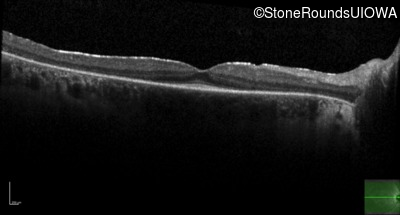

Optical Coherence Tomography - Right -

20/20 -1

Exemplar / OCT Stack

OCT Stack